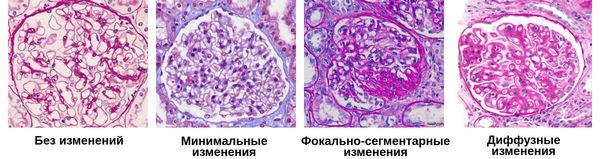

Механизм остро го диффузного гломерулонефрита